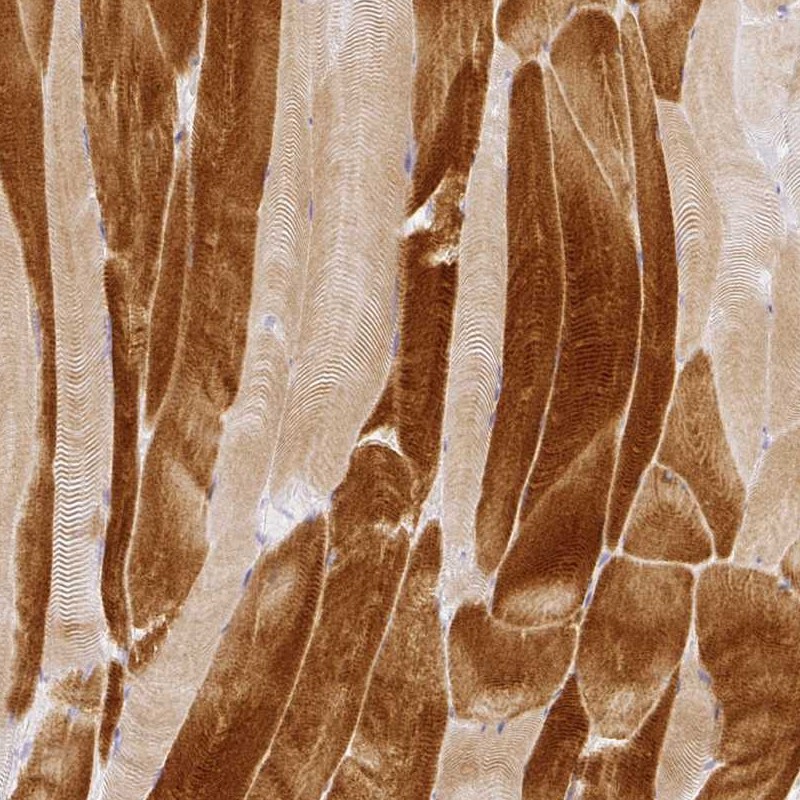

Immunohistochemical staining of human skeletal muscle shows strong cytoplasmic positivity in myocytes.